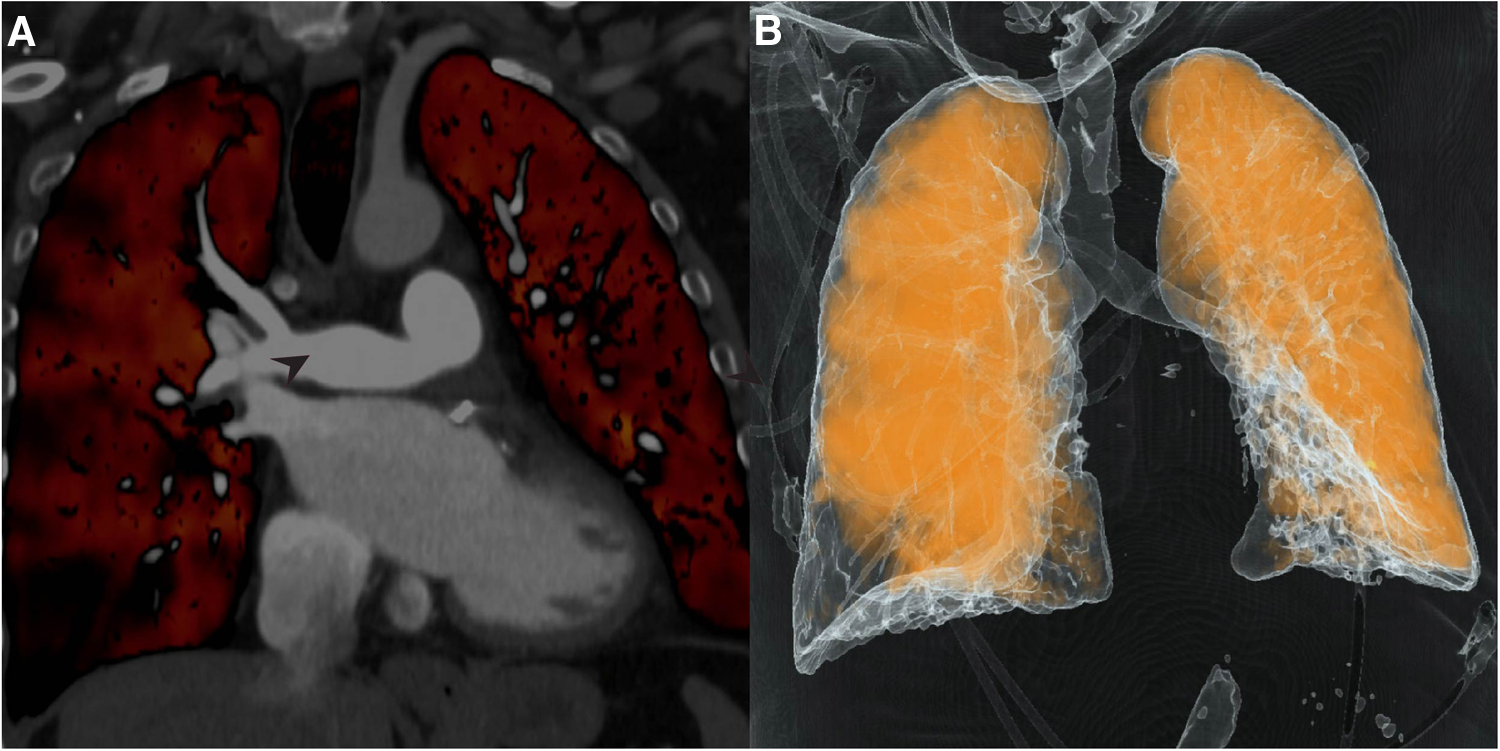

Dual-energy computed tomography (DECT) redemonstrated unilateral complete occlusion of right pulmonary arterial circulation with thrombus propagation into the proximal right pulmonary artery. No filling defects in the left pulmonary arterial system were visualized. Despite the apparent complete obstruction of the right pulmonary artery, perfused blood volume (PBV) mapping of the dual energy CT study revealed areas of the right lung that were still minimally perfused (Figure 1 A,B).

Figure 1

Dual-Energy computed tomography (DECT), pulmonary and coronary angiography. (A) Coronal DECT image demonstrating obstruction of right pulmonary artery (arrowhead); (B) Perfusion mapping demonstrates limited perfusion of right lung from unknown systemic supply at time of imaging. (C) Pulmonary angiography confirmed complete obstruction of right pulmonary circulation (arrowhead); (D) Coronary angiography revealed multiple systemic coronary-pulmonary collaterals from the left circumflex artery (asterisks).